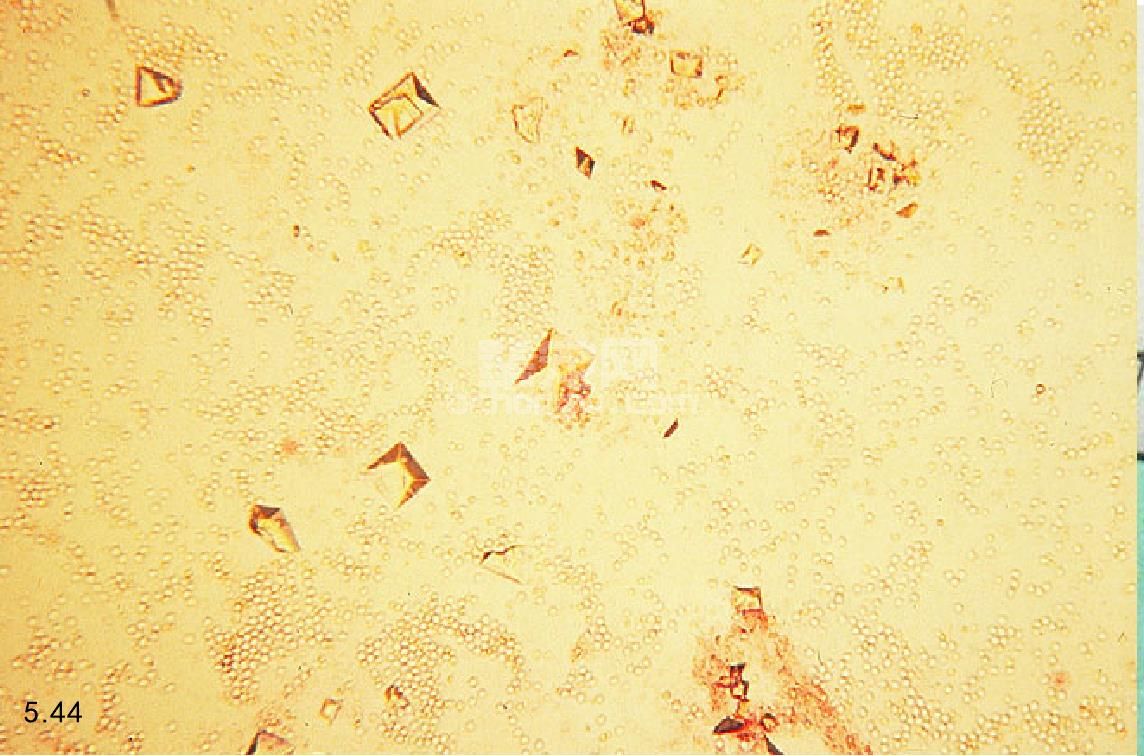

非阻塞性 通过尿液分析和尿液培养以及敏感性试验(对于可疑的很少发生细菌感染的病例)可以确定非阻塞性FLUTD。在尿液沉积物中,很大比例的猫会出现血尿,但是脓尿很少发生(图5.44)。没有出现血尿并不能排除是FLUTD,因为在尿液沉积物检查,正常的情况下用膀胱镜检查时也会见到损伤。尿液沉积物中晶体矿物质类型应引起注意。腹部的X线片检查显示在膀胱内有不透射线的尿结石,如草酸钙,但是双重膀胱造影或者超声检查,有时对检查一些透射线的结石和异物是有必要的(图5.45)。膀胱镜检查可以显示黏膜下水肿和点状的出血,称为团伞状出血,经常与突发性的FLUTD有关(图5.46)。

图5.44 猫下泌尿道疾病时血尿和晶体尿的尿沉积物。